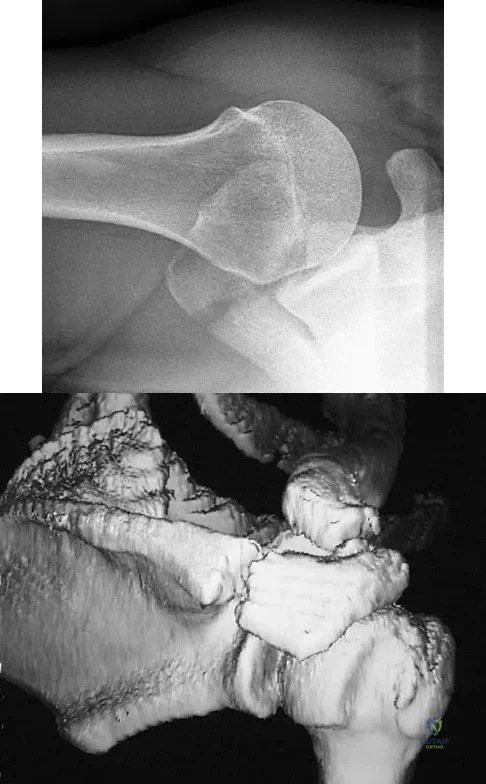

Question 66

A 22-year-old right hand-dominant man who fell off his motorcycle onto the tip of his right shoulder 2 weeks ago now reports pain and difficulty raising his right arm. Examination reveals tenderness and gross movement over the lateral scapular spine and severe weakness during resisted abduction. A radiograph and 3D-CT scan are shown in Figures 24a and 24b. What is the next most appropriate step in management?